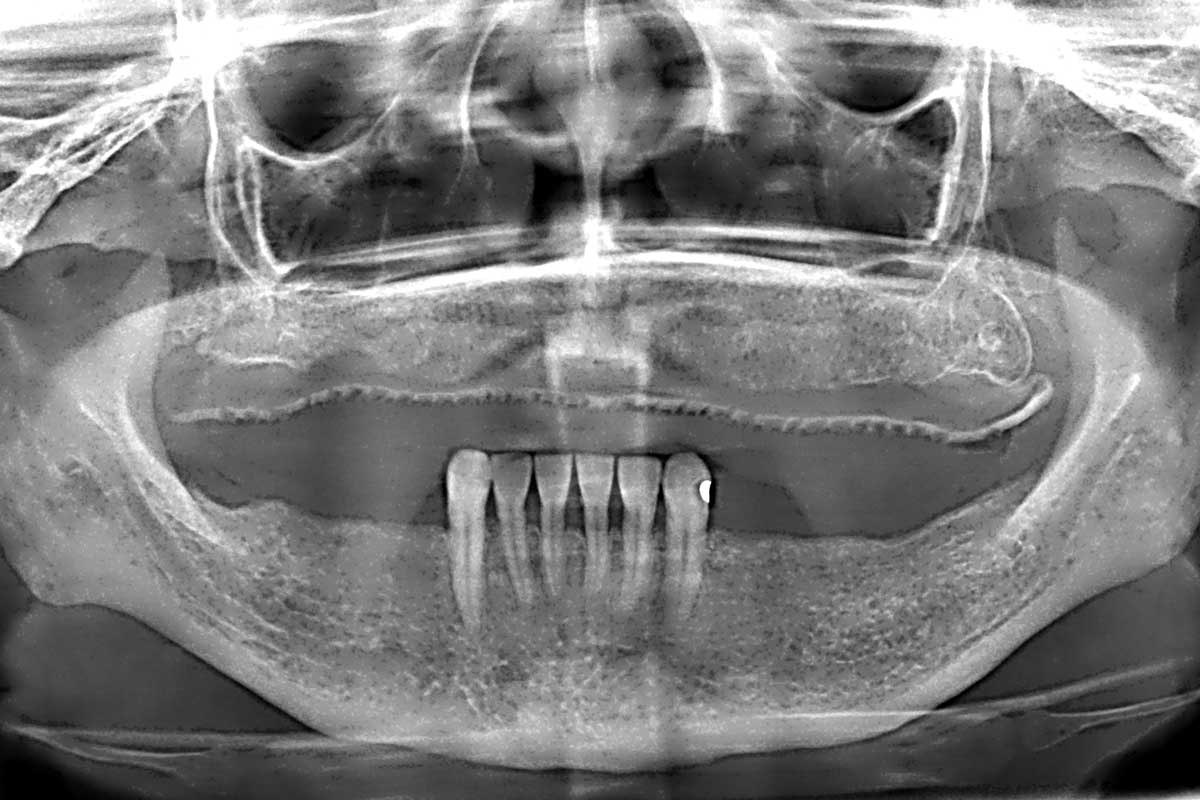

03/31 - Initial OPGFull arch GBR using cerabone®, maxgraft® and Jason® membrane with simultaneous implantation of 6 Straumann® implants - Dres. A. Signorio and G. Molina